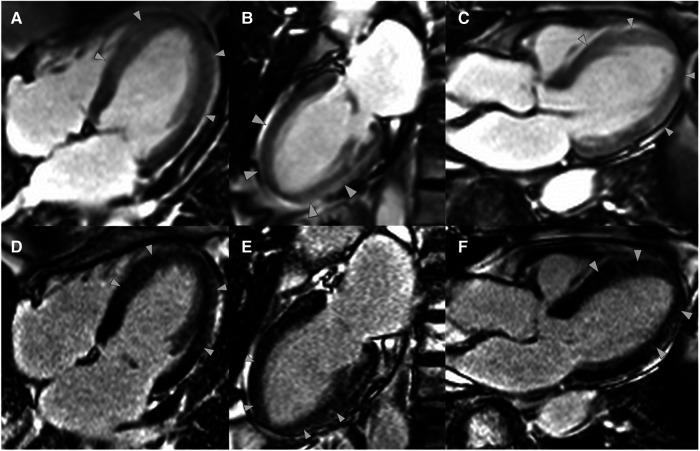

Takotsubo syndrome (TTS) causes angina with ventricular dysfunction that can mimic acute coronary syndrome. Normal coronary angiography leads to cardiovascular magnetic resonance imaging (CMR) in the diagnostic pathway. Historically, TTS was thought to be associated with the absence of late gadolinium enhancement on CMR. This case report highlights the presence of late gadolinium enhancement in a case of TTS while demonstrating the other characteristic findings, including quantitative parametric T/T mapping.

A 69-year-old lady was admitted with chest pain and shortness of breath. She was found to have classical TTS with the characteristic wall motion abnormalities on echocardiogram, left ventricular angiogram, and CMR. Her CMR also demonstrated strongly positive myocardial T/T mapping that matched the wall motion abnormalities and the less frequently described positive early and late gadolinium enhancement.

This case highlights the diagnostic pathway in TTS and the ability of CMR to make a diagnosis in myocardial infarction with non-obstructed coronary arteries. We describe the characteristic cardiac imaging features of TTS while discussing the positive late gadolinium enhancement patterns that may help confirm the diagnosis.

应激性心肌病(TTS)可导致伴有心室功能障碍的心绞痛,其表现可酷似急性冠状动脉综合征。正常的冠状动脉造影检查会促使在诊断流程中进行心血管磁共振成像(CMR)检查。以往认为,TTS与CMR检查时无延迟钆增强有关。本病例报告着重介绍了一例TTS患者存在延迟钆增强的情况,同时展示了其他特征性表现,包括定量参数T/T映射。

一名69岁女性因胸痛和气短入院。经超声心动图、左心室血管造影和CMR检查,发现她患有典型的TTS,伴有特征性的室壁运动异常。她的CMR检查还显示心肌T/T映射呈强阳性,与室壁运动异常相符,且有较少被描述的早期和延迟钆增强阳性表现。

本病例突出了TTS的诊断流程以及CMR对无阻塞性冠状动脉的心肌梗死进行诊断的能力。我们描述了TTS的特征性心脏影像学表现,同时讨论了可能有助于确诊的延迟钆增强阳性模式。